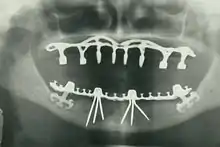

Other practices relevant to evidence-based dentistry include radiology of the mouth to inspect teeth deformity or oral malaises, haematology (study of blood) to avoid bleeding complications during dental surgery, cardiology (due to various severe complications arising from dental surgery with patients with heart disease), etc.

- Oral and maxillofacial radiology – The study and radiologic interpretation of oral and maxillofacial diseases.